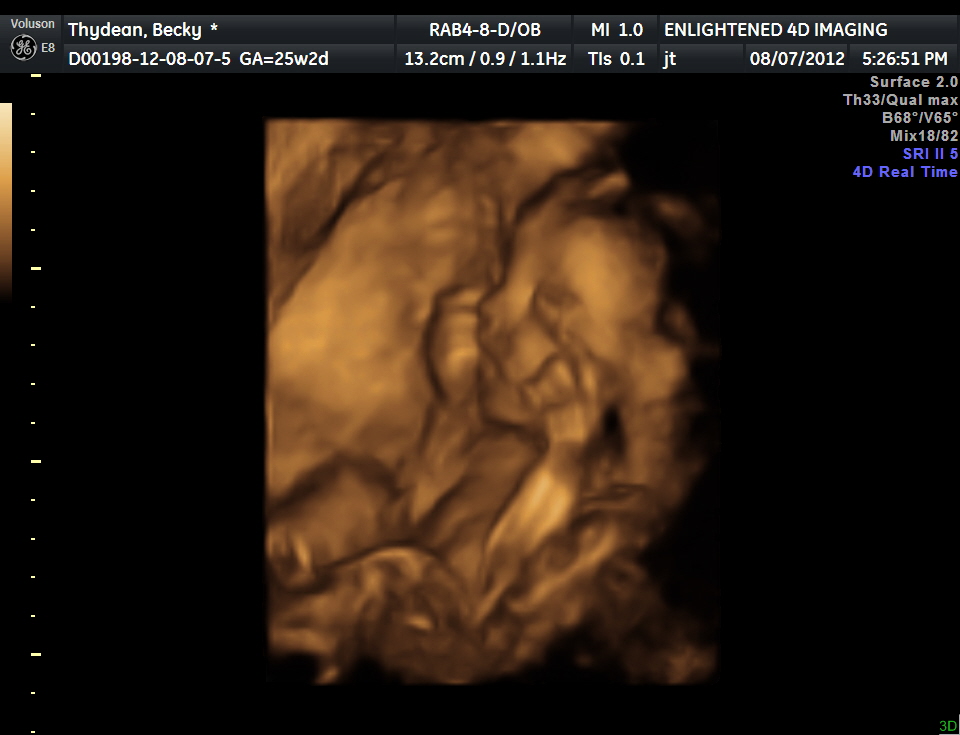

3d 4d Ultrasound Illinois Normal Champaign Lincoln